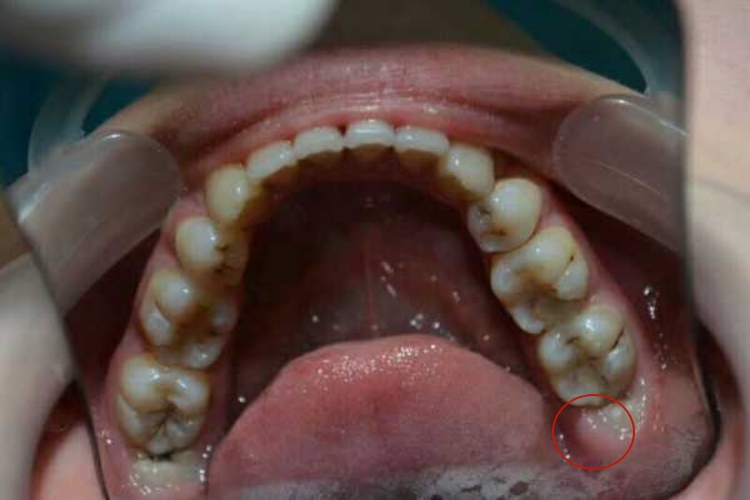

拔完智齿口腔出现白色软肉,表现为创伤周围出现白色假膜或创面出现脓肿。

白色假膜:拔牙后创面愈合过程中,在新生肉芽表面会出现一层白色的假膜,这是为了保护伤口而形成的保护层,类似白色软肉。

感染:表现为拔牙后局部创面存在脓样物质,看似如同白色软肉,考虑出现急性感染,可伴有局部或面部肿胀、疼痛、开口受限等症状。